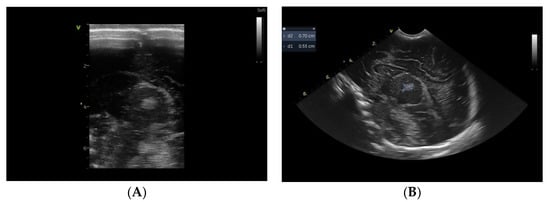

2. Case Report